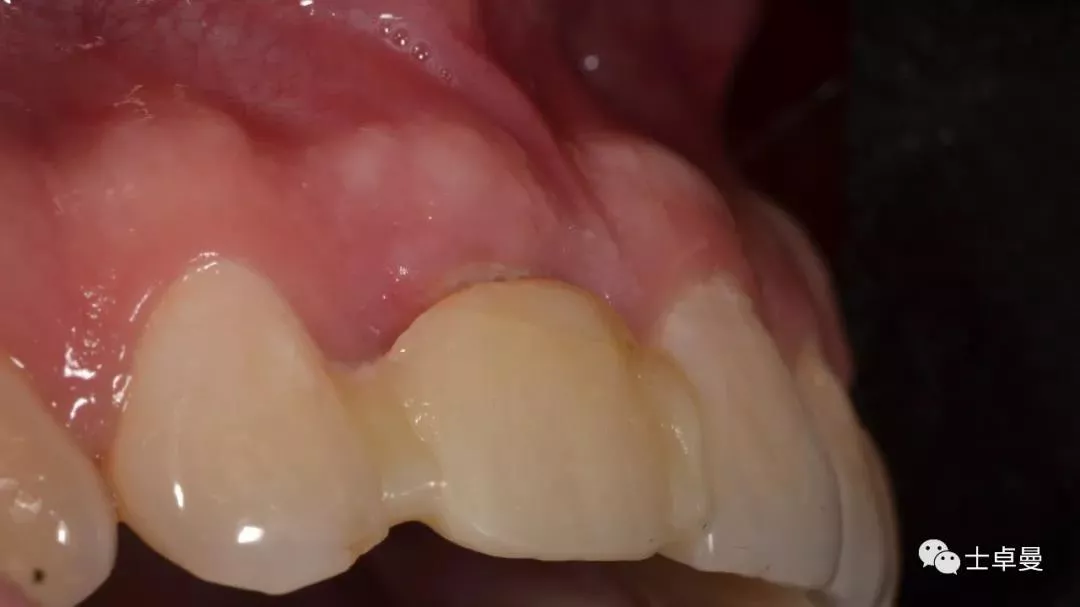

术后4个月复查,软组织无炎症

术后4个月复查,种植体周未见明显暗影

临时修复后2个月,龈缘及龈乳头位置理想,软组织健康

· 2个月后,见唇侧骨弓轮廓可,龈缘及龈乳头形态自然,去11临时修复体,植体ISQ值测定82,个性化取模,试戴Variobase氧化锆基台+LAVA氧化锆单冠,就位被动性良好,增加基台扭力至35Ncm,粘接固位上部冠,调合抛光。

完成永久修复,骨弓轮廓、龈缘及龈乳头形态自然,可见牙龈点彩,修复体外形及色泽可,患者满意。

X线示,永久修复体已就位